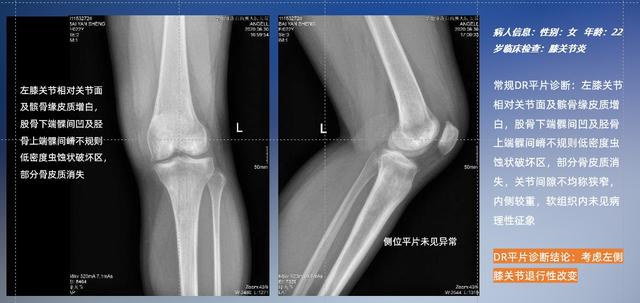

以膝关节疾病检查为例,膝关节在解剖学意义上是一种较为复杂的最大关节,由胫骨上端、股骨下端及髌骨组成。在股骨与胫骨的关节面之间存在两块半月板,分别处于内侧、外侧。膝关节的运动主要为伸、屈,在半屈位时可进行小幅度的旋外、旋内运动。随着现代人们体育生活以及肥胖的增加,膝关节疾病出现高发趋势,特别是关节磨损、膝关节炎与骨关节炎等关节退行性改变,长时间的内翻负荷会造成内侧关节软骨、骨性关节面的磨损。目前针对此类疾病的检查主要为平片下的负重位检查、CT检查以及MRI检查,相较于非负重位检查,负重位检查能更加真实反映膝关节结构中胫骨、股骨、髌骨实际对位关系和关节面的形态特征及关节间隙大小,对膝关节骨关节病诊断准确率高。

普通平片扫描与WR-3D扫描前后诊断结果对比

与此同时,数字化X线摄影技术相较于CTMRI来说,能快速获取真实、直观、满足临床需要的影像。DR的图像具有图像层次丰富、空间分辨力高、影像边缘锐利清晰、密度分辨力高级细微结构表现出色等特点,针对膝关节解剖结构数字化X线摄影技术应用价值很高,尤其是是对骨小梁与骨皮质的显示非常清楚。在负重位状态下,数字化X线三维摄影扫描与重建,能够更好的呈现受检者关节受力改变的状态。尊龙凯时人生就是博科技创新的WR-3D动态三维数字化X线摄影技术,通过数字化X线摄影完成三维扫描并重建三维影像信息,包括MPR多平面重建、MIP重建以及VR绘制。扫描时间短,剂量相较于CT设备大幅缩减,同时成本更低,在临床诊断以及医疗方案制定中具有极大的价值意义。相较于普通平片下的负重位扫描,负重位动态三维扫描摄影技术能够避免二维状态下的组织结构重叠、密度分辨率不足、组织解剖结构难以分辨等问题,WR-3D支持多角度的动态三维摄影观察,能全面的呈现被检查部位在多个角度下三维影像信息,极大的减少了二维负重位检查的漏诊率。